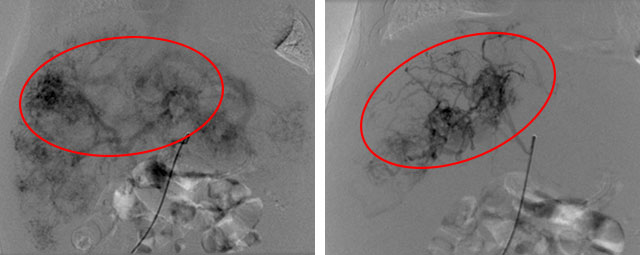

一边积极维持血流动力学稳定,一边积极跟家长沟通病情,并做好术前准备。次日张靖主任主导手术。术中见肝脏多发血管瘤及多发肝动静脉瘘形成,术中给予肝动脉栓塞,再次造影显示动静脉瘘明显减少,手术过程非常顺利。

手术前的造影